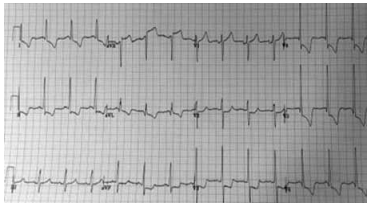

Paciente do sexo feminino, de 65 anos, portadora de hipertensão arterial e dislipidemia mista, chega à sala de emergência com história de dor torácica há três horas, sem fatores de piora. Nega irradiação. Realizou eletrocardiograma mostrado a

seguir, com troponina ultrassensível elevada:

(Arquivo pessoal; imagem usada com autorização)